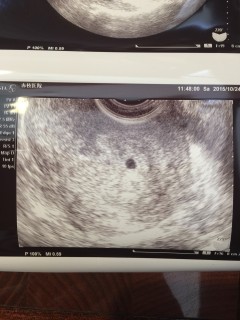

待望の二人目。6週まで待って心拍確認できるようになってからと思ったけど我慢できず受診。 『うん、オメデタですよ~』と言われて嬉しくて何も言えませんでした。10日後には心拍見えるのを期待(*^^*)